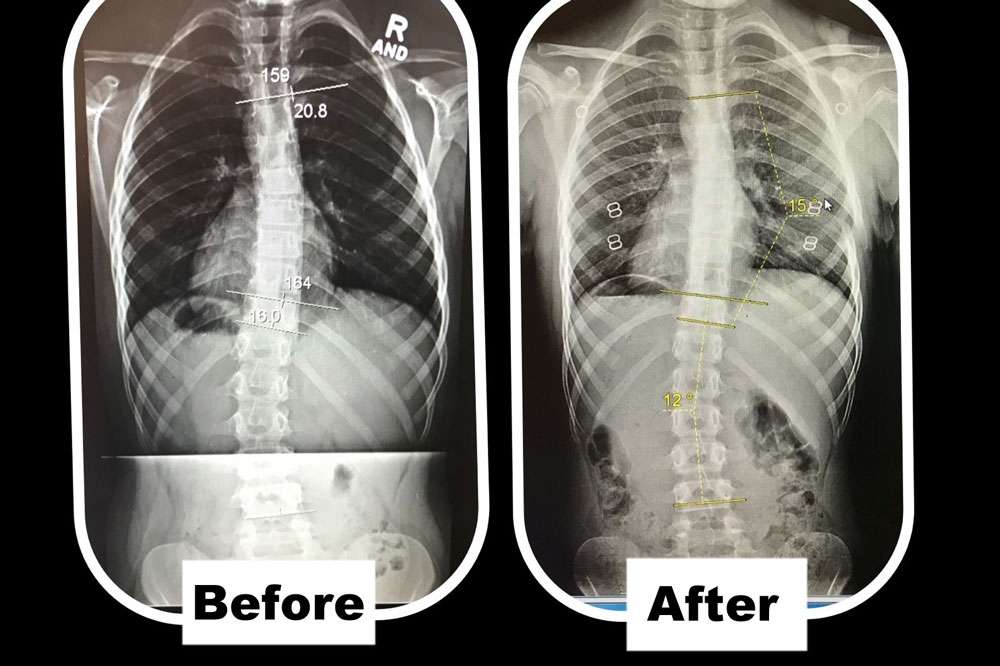

Scoliosis is measured on x-ray as a Cobb Angle. This measurement tells us how bad the scoliosis is and then guides us in how we treat it. Curves under 10 degrees usually aren’t considered scoliosis. Those curves 10-25 are called mild curves and we treat them with scoliosis specific exercise. Curves 25-45 degrees are treated with scoliosis specific exercise and bracing. Those above 45 degrees are usually surgical candidates. There is a measurement error of 3-5 degrees, which means to really have significant change, it needs to be above that.

Here are some examples of what can be done with scoliosis specific exercise with a variety of patients. The main goal of treatment is to STOP progression of the curve. With hard work and dedication we can also see reduction in the curve.